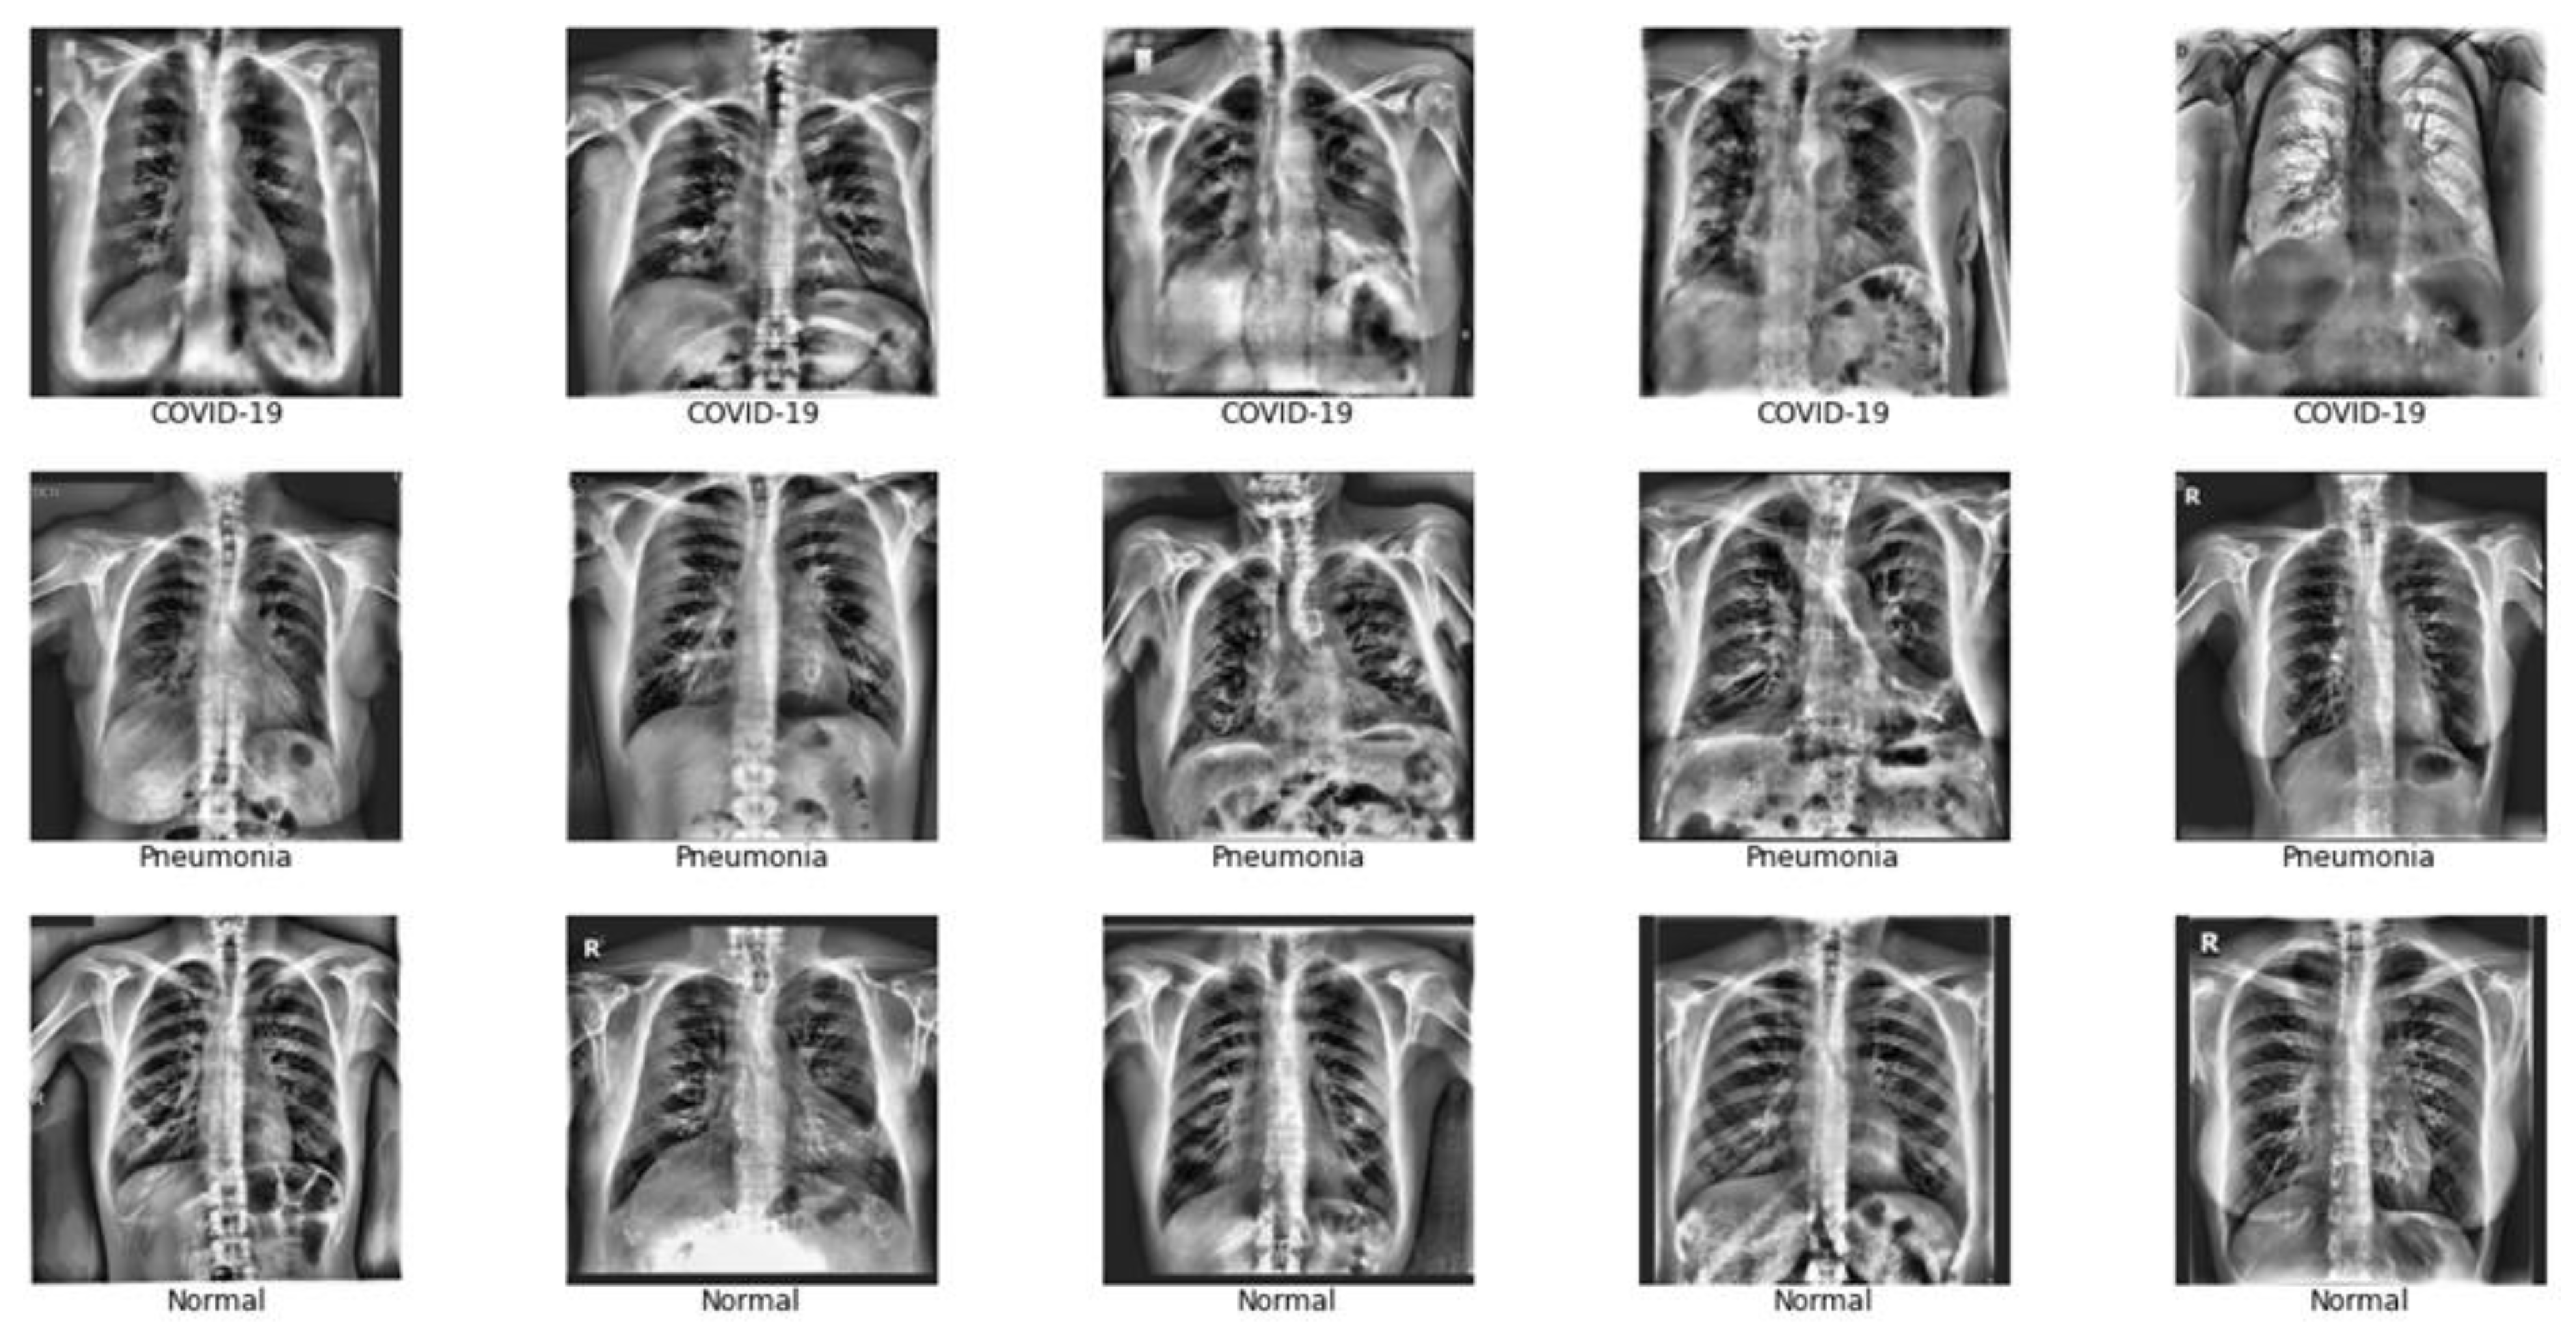

Local contrast and edges were made more visible using computer limited adaptive histogram equalization (CLAHE). This allowed COVID-19 symptoms to be visible in the lungs []. CLAHE is a version of adaptive histogram equalization (AHE). In AHE, the image is divided into tiles, and each tile has its contrast enhanced by considering the pixels in the tile. However, AHE tends to over-amplify noise in nearly uniform image regions. CLAHE overcomes this by limiting amplification []. The transformation of images using CLAHE is shown in Figure 4.

Figure 4.

Pre-processing applied to CXRs. (a) Original image, (b) Pixel re-scaled image (c) Image after CLAHE.